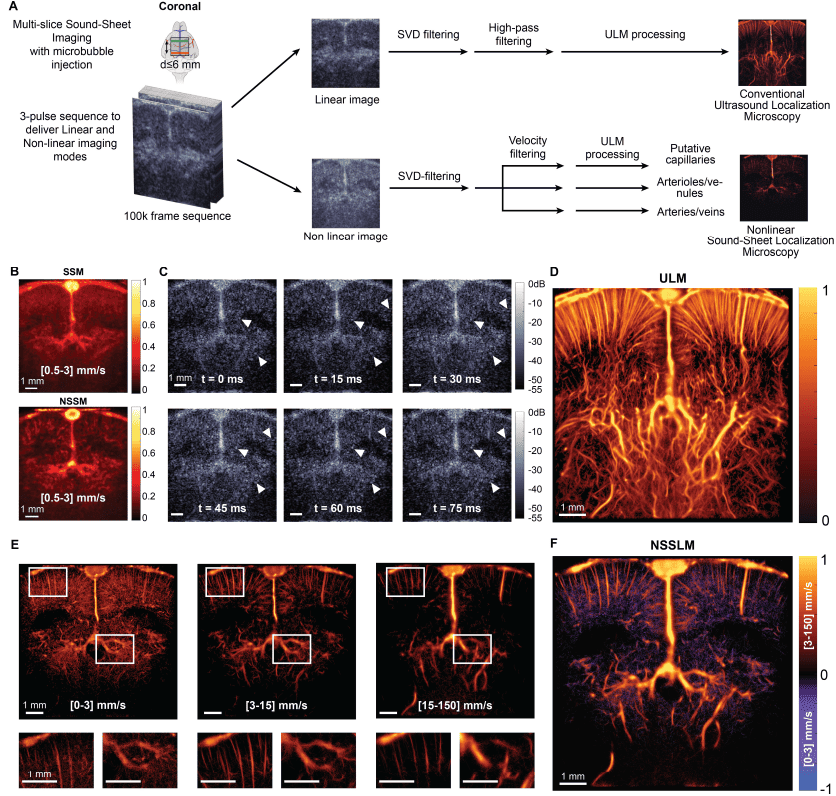

Ученые исследовали нелинейную локализационную микроскопию звукового листа (NSSLM от nonlinear sound-sheet localization microscopy) церебральной капиллярной сосудистой системы (снимки выше). Краниотомированные мозги крыс, перфузируемые MB, визуализировались на частоте 1 кГц с использованием NSSM в коронарной средней мозговой плоскости в течение 105 секунд, что привело к получению 105 кадров (5A). Для генерации современных изображений ULM и изображений NSSLM использовались два конвейера постобработки. Вкратце, обработка NSSLM состояла в фильтрации эхо-сигналов MB с шагом амплитудной модуляции в NSSM, за которой следовала фильтрация по скорости для изоляции MB в нескольких скоростных диапазонах [0-3], [3-15], [15-150] мм/с. Положение отдельных эхо-сигналов MB оценивалось с помощью алгоритма радиальной симметрии, а траектории реконструировались с помощью спаривания Куна-Мункреса. На 5B показаны изображения доплера SSM и NSSM, отфильтрованные в диапазоне скорости капиллярного потока (от 0.5 до 3 мм/с), показывающие, что NSSM извлекает сосудистые сигналы в корковых и гиппокампальных областях мозга крысы с хорошим SNR, тогда как изображения SSM в основном заполнены диффузным сосудистым шумом. В частности, низкие скорости, расположенные на стенке синусной вены, видны в допплеровском NSSM. Временные ряды кадров NSSM, отфильтрованных в диапазоне скорости капиллярного потока (5C), показывают динамику медленно текущих MB, захваченных с помощью NSSM, что составляет основу для постобработки NSSLM. Отдельные микропузырьки, которые являются квазистатичными, обозначены белыми стрелками. В течение 75 мс несколько MB продвигаются менее чем на половину длины волны (57 мкм). Это указывает на то, что их скорость ниже 0.8 мм/с, что попадает в диапазон скоростей капиллярного потока.

В качестве справочного материала ученые обработали современную карту плотности ULM с использованием передачи TX1 последовательности NSSM (5D). Для сравнения, NSSLM (5E–5F) позволил картировать капиллярные русла, сегментированные с полосой скорости потока 0-3 мм/с (левая панель на 5E), артериолы и венулы, сегментированные с полосой скорости потока 3-15 мм/с (средняя панель на 5E) и артерии и вены, сегментированные с полосой скорости потока 15-150 мм/с (правая панель на 5E). Составное изображение NSSLM, показывающее все сосудистые отсеки, представлено на 5F. Сосудистые структуры, отображенные на изображении NSSLM, выглядят явно плотнее структур, обнаруженных с помощью SSLM, как и ожидалось от капиллярных русел.